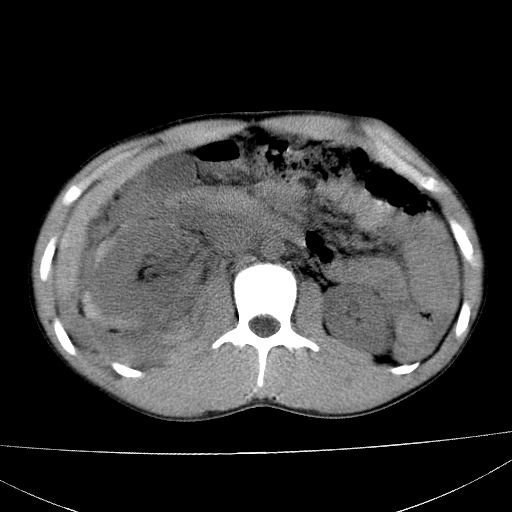

标题: CT15860:男,21岁,腹部外伤2小时伴胸疼。 [打印本页]

标题: CT15860:男,21岁,腹部外伤2小时伴胸疼。

肝脏及肾脏明显有损伤性改变并激发腹腔内积液(血),以肝脏撕裂及肾周积血显著。

1)肝破裂伴腹腔积液(血)。2)右肾破裂伴右肾包膜下及肾周血肿。3)腹部空腔脏器穿孔可能。4)右侧少量胸腔积液(血)。

肝肾挫裂伤,右肾周及包膜下血肿,腹腔积液,不排除空腔脏器穿孔,建议行增强检查

肝、右肾包膜下血肿,右侧腰大肌及腹膜后血肿;腹腔少量积血;腹腔疑有少量游离气体伴肠破裂。

1肝挫伤伴腹腔积液。2右肾挫裂伤伴右肾包膜及肾后间隙肿血肿。3右肾脏周围的积气,十二指肠显示结构不清,考虑十二指肠降部破裂可能性大。